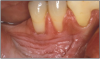

Figure 9 – Gingival Attachment Loss. Image provided by: Dr. JE Bouquot

Figure 9

Smokeless tobacco use can result in halitosis, staining, abrasion of the teeth, gum recession, and dental caries.27 Smokeless tobacco manufacturers add other compounds to their products to achieve the flavors their customers want, such as cane sugar, honey, licorice, or rum and abrasives. These components of smokeless tobacco, along with poor oral hygiene can cause extensive gingival attachment loss and carious lesions on the exposed root surface. Focal gingival recession with periodontal attachment loss and bone erosion occurs frequently on the facial surfaces of the teeth where the tobacco is held. This recession is a result of the irritation caused by the toxic chemicals and abrasives found in smokeless tobacco. It is not uncommon to find substantial amounts of root surfaces exposed at the tobacco placement site. With the root surface exposed, there is an increased risk of hot and cold sensitivity.28 Bleeding is less common because of the vasoconstriction properties of nicotine.27